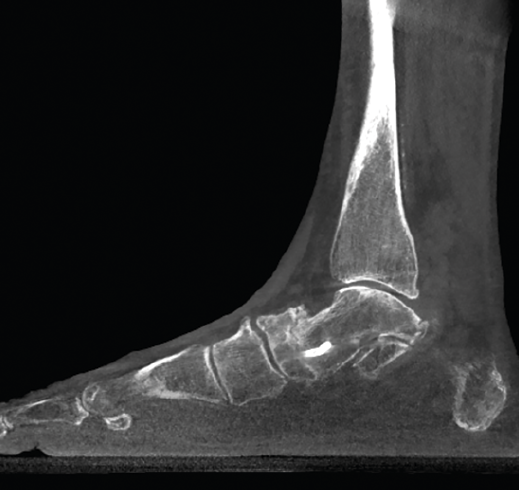

Figura 5. Artropatía de la columna medial en paciente operada de artrodesis astragaloescafoidea.

- Inestabilidad de la columna medial o inestabilidad tarsometatarsiana. Valoración y estudio de la columna medial en carga (Figuras 5 y 6).